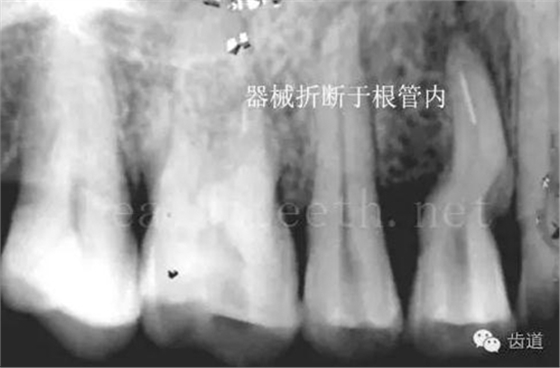

因?yàn)楸旧聿桓阏衬げ?,收集到的病例有限,大多是同事收?/span> 頰粘膜扁平苔蘚 舌粘膜扁平苔蘚 舌緣創(chuàng)傷性潰瘍 長(zhǎng)期戴活動(dòng)義齒不當(dāng)或是戴不良修復(fù)義齒造成的口腔粘膜潰瘍,應(yīng)該引起高度警惕,因?yàn)檫@種潰瘍?nèi)菀装┳?/span> 黑毛舌 舌息肉,該患者同時(shí)伴有胃、食管息肉,后來(lái)看內(nèi)科了,具體情況不詳 四、孩子的牙齒問(wèn)題 乳牙未退,牙根穿出牙齦對(duì)上唇粘膜造成刺激 乳牙滯留,也是孩子在退牙過(guò)程中最容易遇到的問(wèn)題 五、牙齒發(fā)育上的問(wèn)題 變色牙 氟斑牙 釉質(zhì)發(fā)育不全 四環(huán)素牙 牙神經(jīng)治療后的牙齒變色 10歲孩子剛剛萌出的牙齒變色 2、埋伏牙 左上乳3滯留,恒3未見萌出,曲面斷層片顯示牙齒埋伏 通過(guò)CT片確定埋伏牙齒具體的位置,顯示距離左側(cè)上頜竇很近,偏唇側(cè),這為手術(shù)定位提供了方便 手術(shù)中切斷、完整拔出,未損傷上頜竇 其他埋伏牙 3、多生牙 病例1 病例2 病例3,同時(shí)多生兩顆牙齒 4、各種畸形牙 畸形過(guò)小牙 融合牙:恒牙和乳牙都可以發(fā)生融合的情況(兩顆牙齒長(zhǎng)在了一起) 畸形中央尖:在牙齒的中央,兩個(gè)牙尖之間又多長(zhǎng)出一個(gè)牙尖,由于進(jìn)食的磨耗很容易造成磨穿,神經(jīng)就會(huì)與外界相通,出現(xiàn)牙髓炎的癥狀 六、牙齒的外傷 牙冠折斷 牙根折斷 烤瓷牙打樁修復(fù)后牙根折斷 外傷后牙齒的全脫位,應(yīng)該保留牙齒盡早做再植手術(shù) 七、牙齒的慢性損傷 牙頸部楔狀缺損 牙冠劈裂及完整拔除后的情況 牙根縱裂及拔除后的情況 牙隱裂,牙齒表面有肉眼看不到的裂紋,細(xì)菌通過(guò)其進(jìn)入牙髓,容易出現(xiàn)牙髓炎癥狀,嚴(yán)重可以造成牙齒的劈裂 這是一位來(lái)中國(guó)學(xué)習(xí)的俄羅斯大學(xué)生的牙齒,已經(jīng)做過(guò)了根管治療,牙齒咬合面有隱裂,通過(guò)鋼絲結(jié)扎固定,做鑄造金屬冠修復(fù)。 八、牙髓炎、根尖周炎 下面圖片都是慢性根尖周炎的病例,有了齲齒,進(jìn)一步發(fā)展就是牙髓炎,如果此時(shí)沒有得到及時(shí)的治療,疾病會(huì)逐漸發(fā)展破壞到根尖的骨質(zhì),將骨質(zhì)破壞后就在牙齦上出現(xiàn)一個(gè)膿瘺,此時(shí)患者不再感覺到牙齒的疼痛了,往往忽視了治療,但是這種不痛并不是疾病好轉(zhuǎn)了,而是因?yàn)榧膊〉难仔詽B出得到了引流,這個(gè)膿瘺會(huì)出現(xiàn)有時(shí)候變大了,有時(shí)候又變小了,但是如果不治療是不會(huì)自己愈合的,只有經(jīng)過(guò)完善的根管治療后才有好轉(zhuǎn)的可能,但是在疾病的治療中時(shí)間是起決定作用的,時(shí)間拖得越晚,好轉(zhuǎn)的可能性越小,經(jīng)過(guò)根管治療后如果膿瘺還是沒有消失,就需要做根尖刮治術(shù),如果仍然沒有好轉(zhuǎn),就只能做根尖切除術(shù)了,這對(duì)牙齒的穩(wěn)固是不利的。下面圖片中在膿瘺中插入了一個(gè)牙膠尖,是我們做根管充填用的材料,是非常軟的,就是在口腔牙齦瘺管的地方插進(jìn)去,通過(guò)拍牙片可以清晰地看到它到達(dá)的位置,從而確定發(fā)病的牙齒,此處是為了讓大家看得更清楚。 門牙兩個(gè)膿瘺 烤瓷牙修復(fù)后牙齦出現(xiàn)兩個(gè)膿瘺,插入牙膠尖,牙片顯示牙膠尖到達(dá)的位置就是根尖炎癥的位置,根尖骨質(zhì)密度降低(發(fā)黑的地方) 牙齒根尖膿瘺,治療前、中、后的圖片對(duì)照,完善根管治療后膿瘺明顯消失了 牙髓炎和根尖炎治療的關(guān)鍵就是根管治療 合格的根管充填治療 不良的根管充填治療 九、關(guān)于智齒(第八顆牙) 四顆長(zhǎng)不出來(lái)的智齒 智齒反復(fù)發(fā)炎造成的頰瘺,膿腫切開引流后面部會(huì)留疤 智齒造成的頜骨囊腫,手術(shù)切除后需要植骨 十、各種錯(cuò)合畸形 開合 深覆合 深覆蓋,上頜前突 反合(地包天) 牙齒排列擁擠 來(lái)源:牙醫(yī)愛看的 KQ88口腔醫(yī)學(xué)網(wǎng)